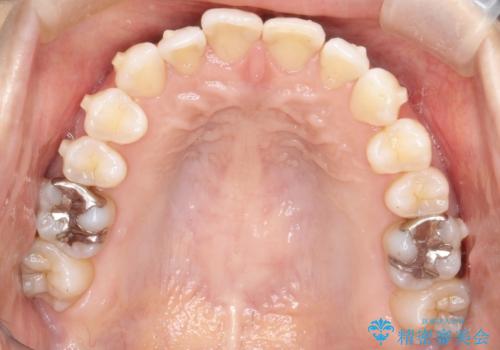

八重歯と前歯のガタガタをインビザラインで

- 八重歯と前歯のガタガタを主訴に来院されました。

目立たず矯正したいとのことでインビザラインで矯正することとしました。

インビザラインで目立たずに治療を終えることができ、喜んでいただけました。